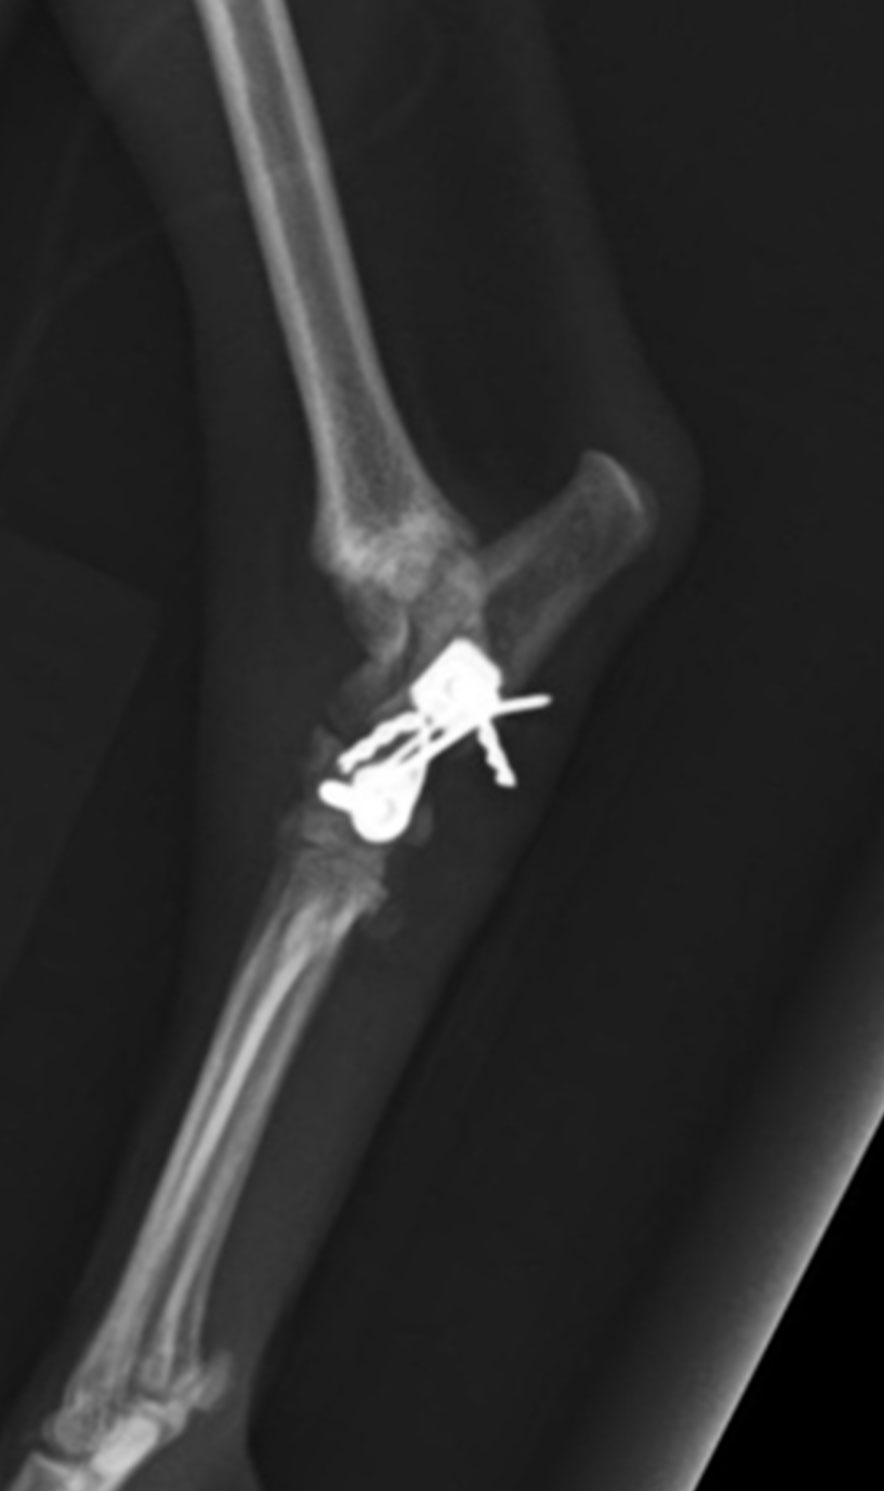

犬種:ポメラニアン、年齢:10ヶ月齢、体重:2.2kg、性別:オス

椅子から落下し右前腕の橈骨と尺骨を骨折した症例です。

術前計画で骨の大きさ、入れるプレート・スクリューを確認します。

手術は観血的に骨の変位を整復し、プレートとスクリューで内固定しております。この症例ではSynthesのプレート(LCP1.5)とスクリュー(コーテックスクリューとロッキングスクリュー)をハイブリットで使用しております。

術前レントゲン検査 術前計画 術後レントゲン検査

側面像 側面像 側面像

頭尾側像 頭尾側像 頭尾側像